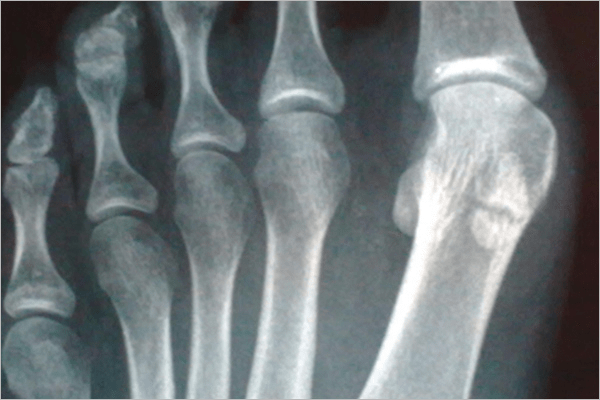

El Ultrasonido, Resonancia Magnética Nuclear, Radiografías, etc pertenecen a esta especialidad médica.

Imagenología/Radiología